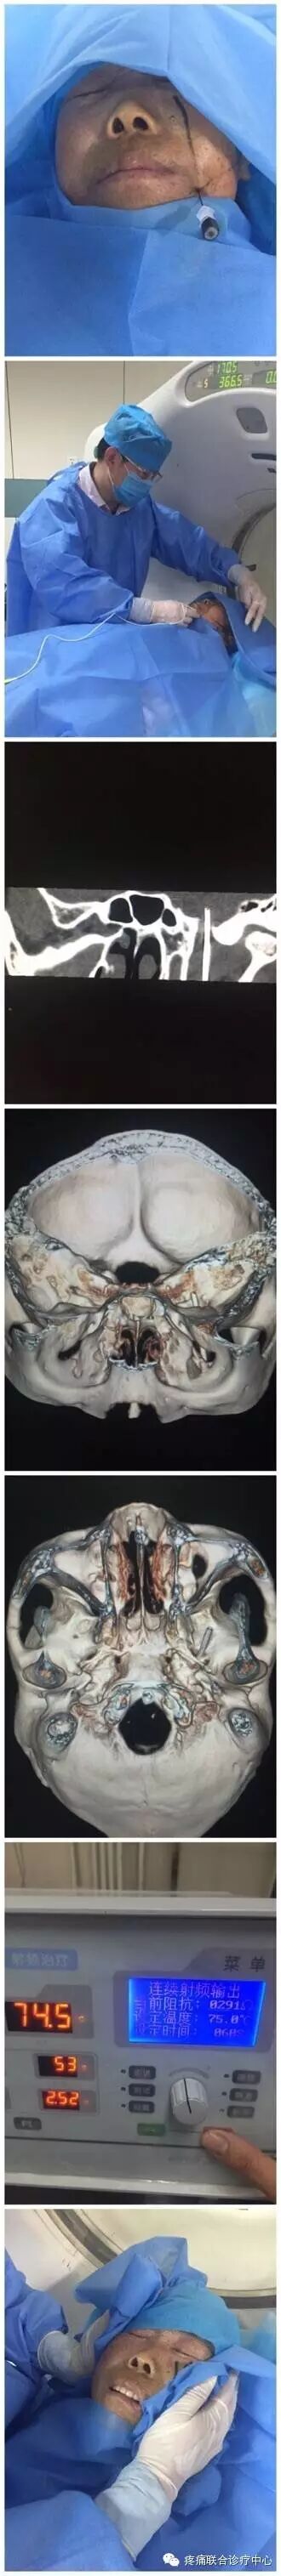

术前完善血尿常规、凝血四项、心电图、血糖、肝肾功能等检查,术前半小时肌注硫酸阿托品注射液0.5 mg,术中静注抗生素以预防感染。患者取仰卧位,头稍后仰。监测心电、血压等变化。背部贴附射频仪的负极板。患侧面颊部,局部消毒铺巾。局麻后,采用Hartel前入路穿刺方法[2.3、6、7]。穿刺点位于患者口角外下2.5cm(A点)、患侧外耳道前结节B点及同侧瞳孔位置(C点),三点做AB及AC连线与面部垂直的两个平面的交线即是穿刺进针的方向。当穿刺针到达卵圆孔部位,在C形臂X线机投照或CT导向下,取颏斜位,增强器向头端旋转30°~35°,向健侧旋转15°~20°可显露出患侧卵圆孔,进针6.0~8.5cm深度时,刺入Meckel囊时有突破感。射频电极自动测量阻抗一般为250~360Ω。若穿刺针进入Meckel囊可见脑脊液流出,此时应将穿刺针后退2~3mm。然后分别进行感觉和运动功能的方波电流刺激并采用电生理监测验证电极位置。术中C形臂定位(图1、2);CT定位(图3、4)。靶点准确定位后进行射频治疗[3、8]。为了达到手术操作无痛,术中常规使用丙泊酚1~2 mg/kg静脉麻醉,并可在术中唤醒患者,以检查面部皮肤痛觉减退的范围。若病变累及多个部位者,宜进一步行相应周围支的射频热凝治疗[3.9]。术后卧床4h,应用抗生素2d。一般术后2~3天症状消失出院。